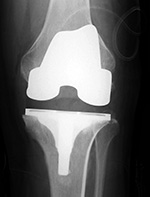

Left knee cruciate substituting revision total knee prosthesis   Cruciate substituting total knee prosthesis and patellar resurfacing.

Left knee cruciate substituting revision knee arthroplasty Left knee cruciate substituting revision total knee arthroplasty Cruciate substituting knee prosthesis - AP view Cruciate substituting knee prosthesis - latera view

46 year-old man with knee revision arthroplasty   Note the large distal femoral box. There is a surgical drain in the suprapatellar space. From Taljanovic, 2005